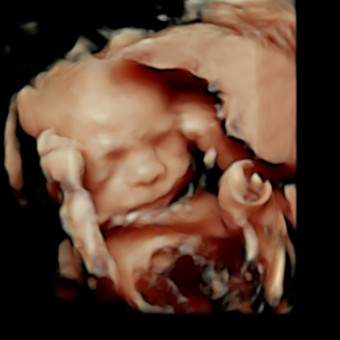

Gabrielle's Baby Registry

Gabrielle & Lewis Finch

We can’t wait to celebrate baby Finch with all of you! 😄